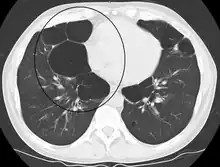

| Advanced centrilobular emphysema showing total lobule involvement on the left side | |